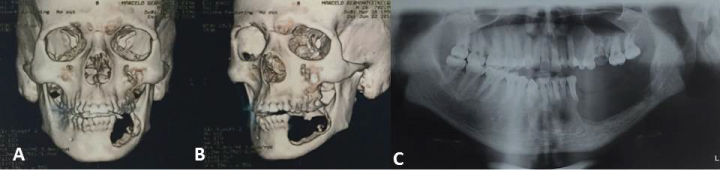

After the diagnostic confirmation, surgery was performed under general anesthesia for the marginal resection of the mandible with a margin of safety to avoid recurrence (Figure 3B). For such, an incision was made in the region of the posterior mandibular alveolar ridge and mucoperiosteal detachment to demarcate the area of resection to be performed with chisels and a mallet. A submandibular incision was also performed, and osteotomy was achieved with the use of a reciprocating saw (Figure 3A). The left mandibular first and second premolars were included in the area of the resection (Figure 3B, Figure 4A, Figure 4B and Figure 4C).

Figure 3: A) Submandibular surgical access with marginal osteotomy; B) Surgical piece of sectioned area; C) Histological cut revealing fragments of hypercellularized young connective tissue with intense monocellular inflammatory infiltrate, hemorrhagic exudate and multinucleated giant cells, confirming diagnosis of central giant cell granuloma. View Figure 3

Figure 4: A,B) Computed tomography reconstruction revealing area of resection; C) Panoramic radiograph after marginal resection. View Figure 4